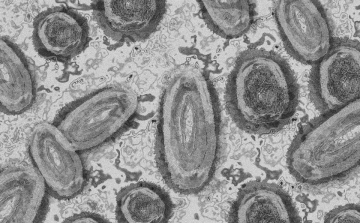

Megfertőződött a majomhimlővel egy gyerek Németországban

Megfertőződött majomhimlővel egy négyéves kislány Németországban - jelentették kedden német hírportálok az országos közegészségügyi intézet (RKI) adatai alapján.